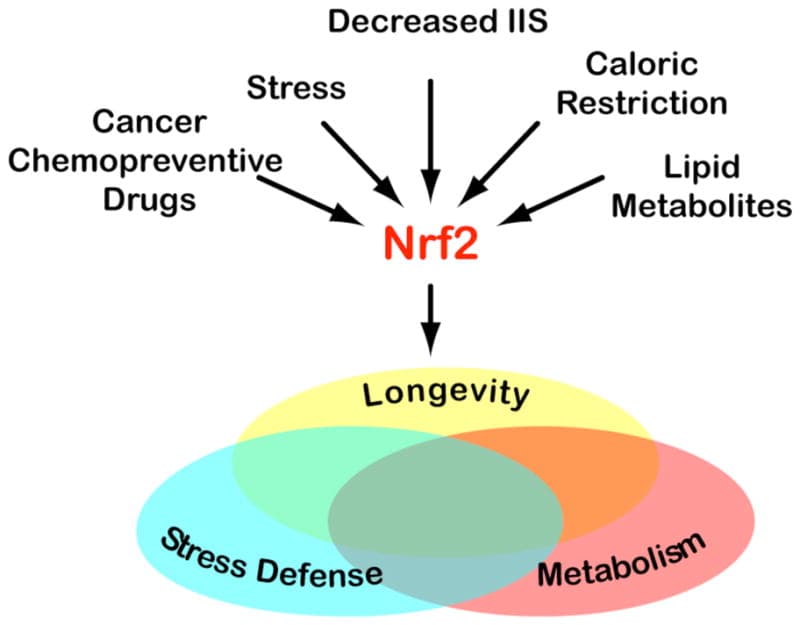

7. Has Anti-Inflammatory Properties

CB2 receptors are expressed in several types of inflammatory cells and immunocompetent cells. R

Activating CB2 receptors inhibit the release of proinflammatory factors. R

CBD treatment resulted in an increase in BDNF expression in the hippocampus and decreased levels of proinflammatory cytokines in the hippocampus (TNF-α) and prefrontal cortex (IL-6). R